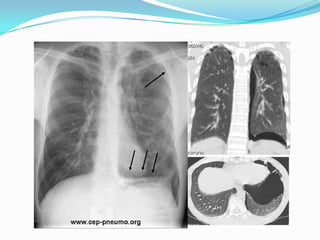

Pneumothorax PNO:

 Dl latérothoracique, brutale, spontanée ou post

traumatique, en coup de poignard, augmentée par

inspiration profonde et toux, accompagnée de dyspnée

 Dg évoqué par examen clinique qui met en évidence

tympanisme et diminution voire silence auscultatoire.

 Radio pul confirme le Dg: hyperclarté partielle ou

totale.

 Le trt est l’excuflation en urgence voire drainage

thoracique